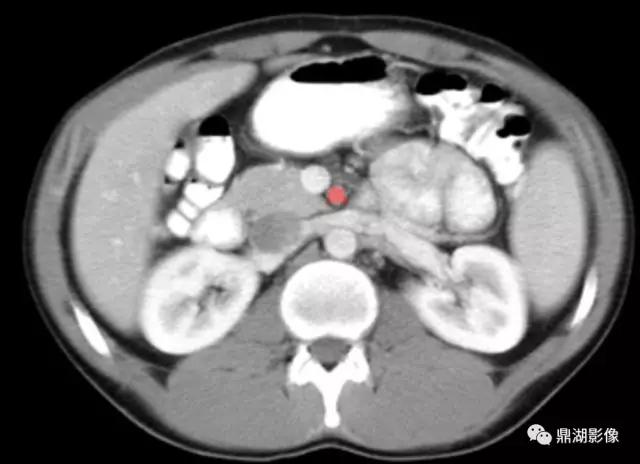

肝曲(Hepatic Flexure)

肠系膜上动脉(Superior Mesenteric Artery)

肠系膜上静脉(Superior Mesenteric Vein)